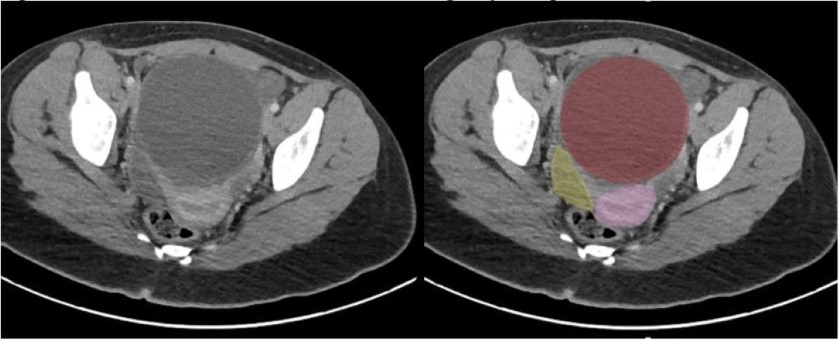

A 13-year-old previously healthy female with no past medical history presented with 4 days of right lower quadrant pain. She had complete resolution of her pain after Motrin and a benign abdominal exam, so she was discharged home. She returned 4 days later with right lower quadrant pain, nausea, and vomiting that had reoccurred at 4 am that morning. A point-of-care ultrasound (POCUS) was performed and showed a normal bladder and no hydronephrosis. She had a normal transabdominal pelvic ultrasound for torsion and a non-diagnostic appendix ultrasound performed by radiology (Figure 1).

Figure 1: Transabdominal Ultrasound. Red: Hemorrhagic Hydrosalpinx; Pink: Uterus; Yellow: Bladder